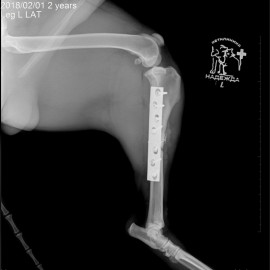

Наш пациент после автотравмы. Был проведен остеосинтез левой голени, в ходе которого была установлена динамическая титановая пластина с винтами. Так же были наложены серкляжные швы из титановой проволоки. Состояние пациента хорошее. Лапой пользуется активно.

Снимок 3-4 после операции